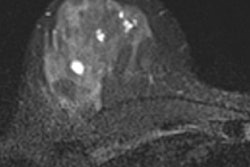

In the second article, breast imaging pioneer Dr. Christiane Kuhl discusses how false positives on breast MRI can be valuable. "Over recent years, the allegedly limited specificity of breast MRI has been refuted by data, which confirm that the positive predictive value of MRI is as high as that of mammography," she said. "Moreover, even though MRI and mammography can cause 'false-positive' diagnoses, we found the prognostic implications of false-positive diagnoses in mammography and MRI may not be equivalent." Read more.